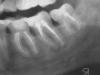

katalex Опубликовано 1 марта, 2008 Поделиться Опубликовано 1 марта, 2008 (изменено) Извините, вопрос, возможно, повторяется.Имееются 6-7 нижние зубы справа (или 36-37, либо 46-47, я не специалист), на них кисты. 1. Кто в Петербурге занимается резекциями (или лечением кист) на таких зубах? Меня сразу к хирургу направили, либо удалять 6-8, либо резекция.2. Это не слишком опасно, там вроде канал с нервом совсем рядом проходит?Снимок (уже старый, от 4 февраля и получилось не очень четко) приложил.Заранее благодарю за ответ. Алексей Изменено 1 марта, 2008 пользователем katalex Ссылка на комментарий

Bier Опубликовано 1 марта, 2008 Поделиться Опубликовано 1 марта, 2008 Скажите, у Вас полностью восстановилась чувствительность? Самому удалил восьмерку - пол-языка ничего не чувствует уже 2 недели за 3 года не полностью. Но уже почти. Извините, вопрос, возможно, повторяется.Имееются 6-7 нижние зубы справа (или 36-37, либо 46-47, я не специалист), на них кисты. 1. Кто в Петербурге занимается резекциями (или лечением кист) на таких зубах? Меня сразу к хирургу направили, либо удалять 6-8, либо резекция.2. Это не слишком опасно, там вроде канал с нервом совсем рядом проходит?Снимок (уже старый, от 4 февраля и получилось не очень четко) приложил.Заранее благодарю за ответ. Алексей если терапевт отказывается их перелечить, я бы заменил на имплантаты. Ссылка на комментарий

katalex Опубликовано 2 марта, 2008 Поделиться Опубликовано 2 марта, 2008 (изменено) если терапевт отказывается их перелечить, я бы заменил на имплантаты.К терапевту я еще не попал, меня сразу к хирургу сплавили.Такой вот вопрос еще по снимку: Каналы пломбировались еще в 1999-2001 г., возможно по "...-формалиновому способу" (я не знаю, как это точно называется).Можно ли делать сразу резекцию корня, или надо все-таки вначале каналы перепломбировать?Меня несколько настораживает такое отношение хирурга...сразу под бор-машину. Изменено 2 марта, 2008 пользователем katalex Ссылка на комментарий